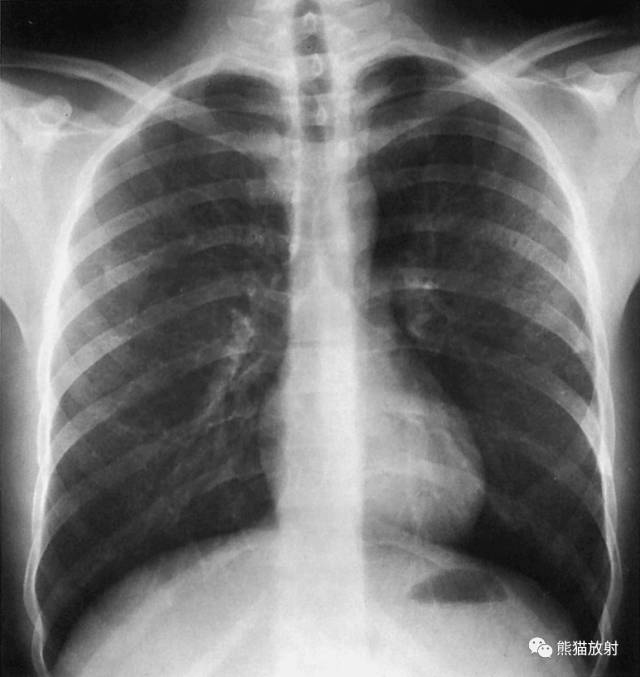

X线平片肺叶/段分布

上叶【S1:尖段、 S2:后段、 S3:前段】

中叶【S4:外段 、S5:内段】

下叶 【S6:背段、S7:内基底段、S8:前基底段、S9:外基底段、S10:后基底段】

左肺

上叶【S1+2:尖后段、S3:前段、S4:舌叶上段、S5:舌叶下段】

下叶【S6:背段、S7+8:前内基底段、S9:外基底段、S10:后基底段】